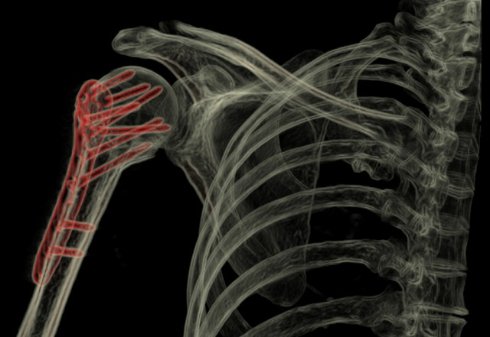

В чём заключается уникальность данной разработки? В способности трёхмерного фото человеческого организма.

Теперь, благодаря инструменту Revolution CT, появилась возможность получать послойные снимки в трёхмерном изображении, путём сканирования человеческого тела.

Новый инструмент сканирования , сердца, кровеносных сосудов и других частей тела предоставит врачам больше информации о состоянии пациента.